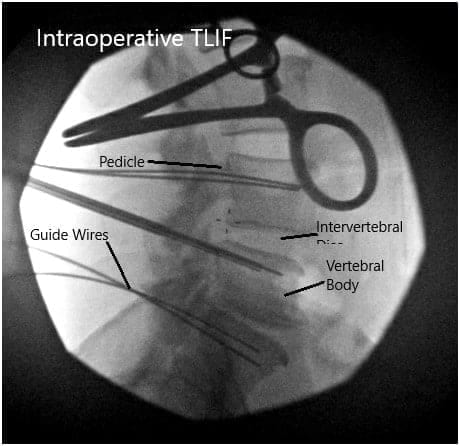

We then used blunt dissection to split the muscle fibers and palpated the edge of the transverse process. Once we are satisfied with the positioning on the fluoroscopic imaging, we then proceeded to use a Jamshidi needle onto the lateral tips of the facet joints except for the L4 region where it was placed along the corner of the transverse process and the facet in order to avoid injuring the L3-L4 facet joint.

All needles were placed under fluoroscopic imaging and once we were satisfied with the positioning, we then evaluated his nerve monitoring and found there to be no changes within any of the needle positions. We then proceeded to place a guidewire into the vertebral body and then removed the Jamshidi needle.

We then secured the guidewires onto the edge of the patient’s bed and turned our attention towards performing the decompression and interbody fusion procedures. We then used a microscope to began our decompression at the L4-L5 region.

Intraoperative Fluoroscopic Images.